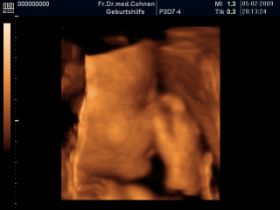

3D Aufnahmen